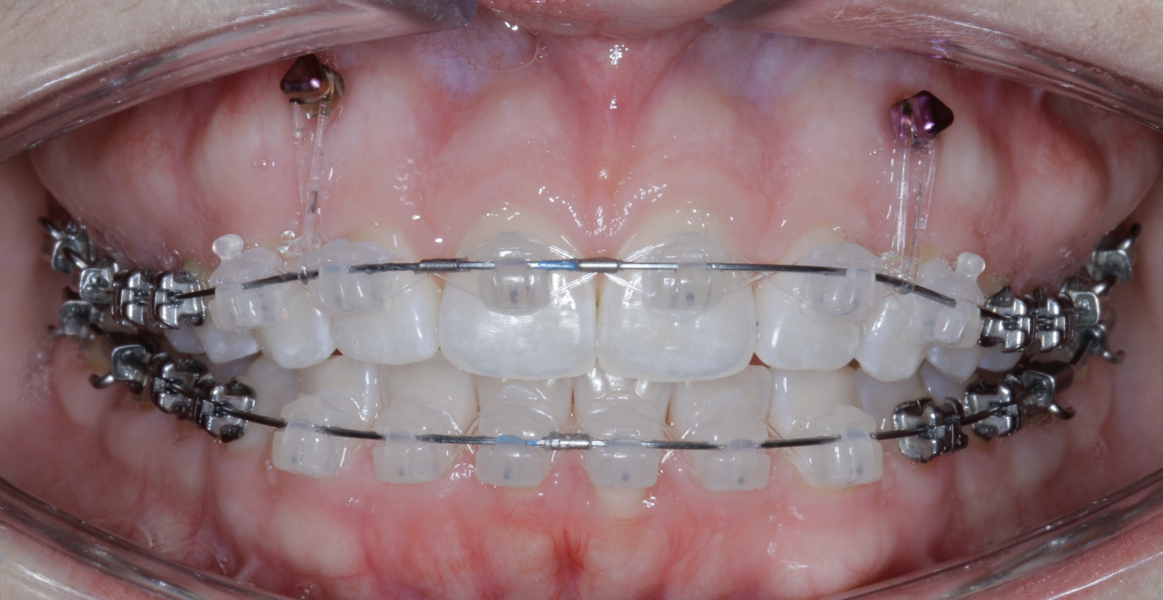

New Age orthodontics and orthopaedics with temporary anchorage devices